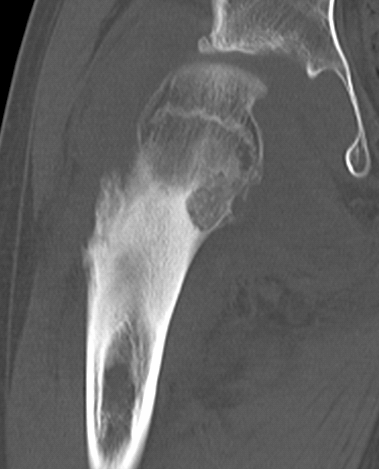

▌膨胀性破坏

膨胀性破坏是地图样破坏的特殊形式,影像学表现为骨质破坏区骨膨胀,周围可见不同程度扩张的骨壳(图 5、图 6、图 7、图 8)。膨胀性破坏是由于肿瘤从骨皮质内面破坏,骨外膜增生形成新生骨造成膨胀的。引起膨胀性破坏见于大多数良性肿瘤和肿瘤样病变如单纯性骨囊肿,动脉瘤样骨囊肿、内生软骨瘤和软骨粘液纤维瘤等,少数也可见于恶性肿瘤如转移瘤、骨髓瘤等。

图 6.膨胀性破坏:骨巨细胞瘤